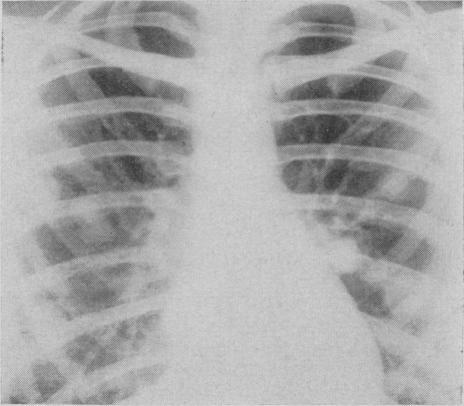

Pulmonary histoplasmosis.

Can Med Assoc J. 1959 Sep 15;81(6):486-8.